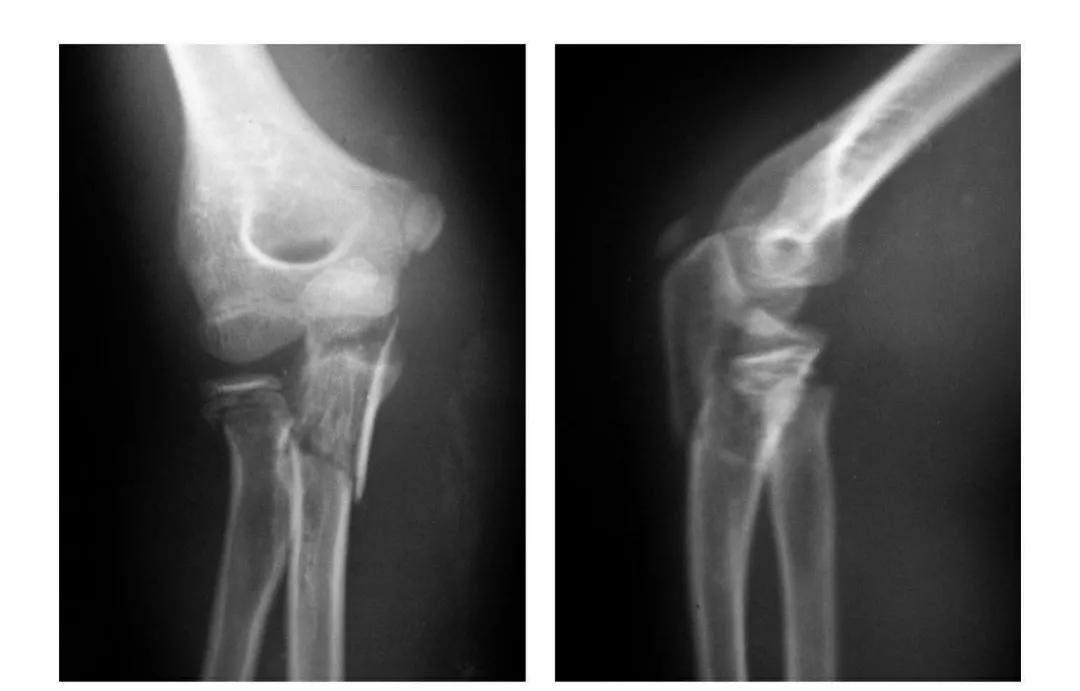

肱骨下端双髁骨折

例1:肱骨内髁及外髁骨折,该两髁骨块均呈向内、外翻转移位。

例2:肱骨内上髁Ⅲ度骨折并外上髁撕脱骨折。

例3:肱骨内上髁Ⅳ度骨折并外上髁撕脱骨折。